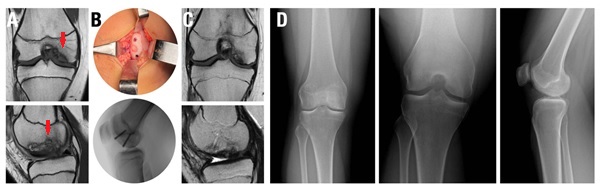

Figura 2. Fijación híbrida en una paciente de 14 años con osteocondritis disecante juvenil localizada en el cóndilo femoral medial. A) RNM DPFS sagital y coronal que demuestra lesión inestable de gran tamaño (flecha roja). B) Imagen intraoperatoria durante la colocación de un injerto osteocondral de 8 mm y 2 tornillos canulados. C) RNM a los 6 meses de evolución, luego del retiro del material de osteosíntesis, se evidencia la curación de la lesión y la incorporación del injerto. D) Radiografías de frente, túnel y perfil donde se observa la resolución completa de la lesión.

En promedio, se trasplantaron entre 1 y 3 injertos osteocondrales cilíndricos por rodilla, con un diámetro promedio de 8 mm (rango, 6-10 mm). Diecisiete rodillas se trataron para DC (Fig. 1) y 16 mediante FH (Fig. 2) de lesiones osteocondrales inestables. Las lesiones tratadas con la técnica DC tuvieron un tamaño promedio de 132 mm2, significativamente menor que las lesiones de FH, con un tamaño promedio de 404.1 mm2 (p <0.0001). El seguimiento promedio de la cohorte fue de 20.5 meses (rango, 6-80 meses). No se registraron complicaciones perioperatorias.